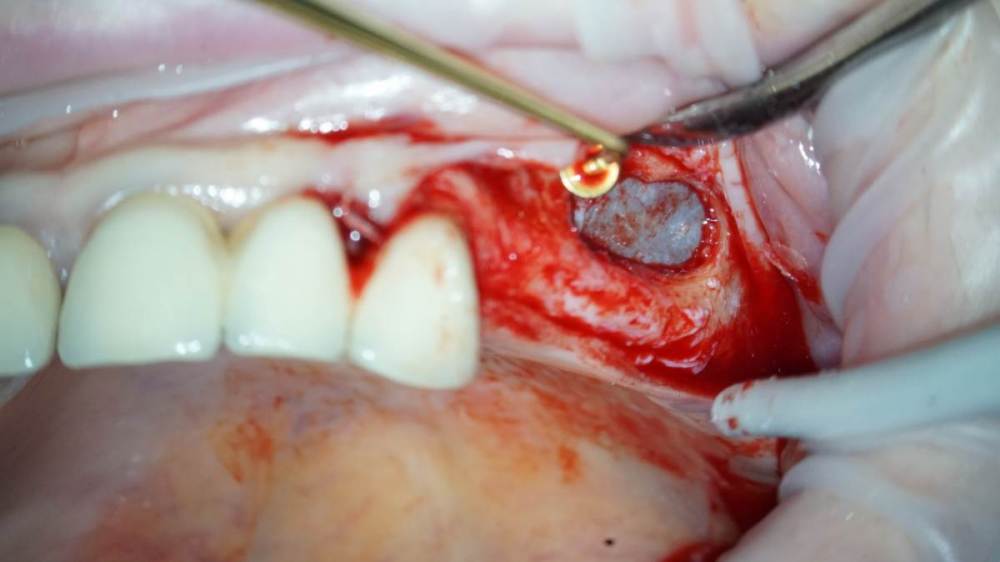

TIGER Опубликовано 18 февраля, 2022 Поделиться Опубликовано 18 февраля, 2022 Приветствую коллеги!Небольшой кейс с удалением кисты и синусом.Произведено :удаление кисты,синус-лифт ,через 4 месяца имплантация,ещё через 4 протезирование 5 1 1 Ссылка на комментарий